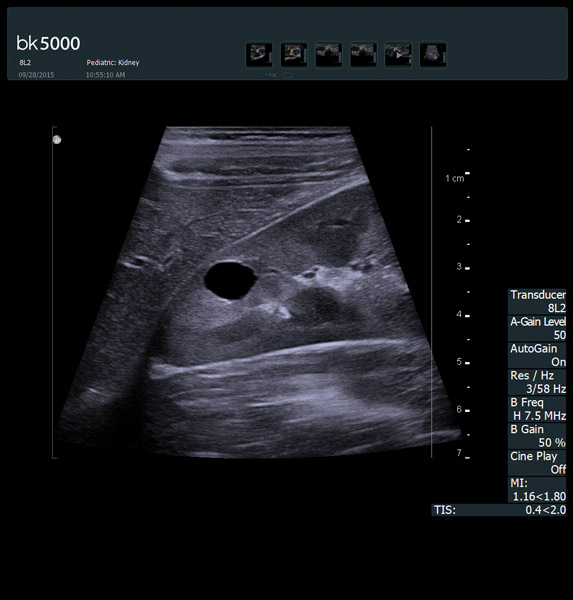

You know what you need, and you need it fast. That’s why the bk5000 is designed to deliver the high resolution images you count on quickly and efficiently. Whether you’re identifying margins of a lesion or making a general assessment of an area of interest, the bk5000 has the power and performance to meet your needs on your terms.

From the simplest diagnostic imaging to the most critical interventional procedures, every clinical situation has its own set of unique challenges. The bk5000 offers a full suite of innovative technologies and advanced controls and adjustments to help you achieve the best possible image quality, across many applications.